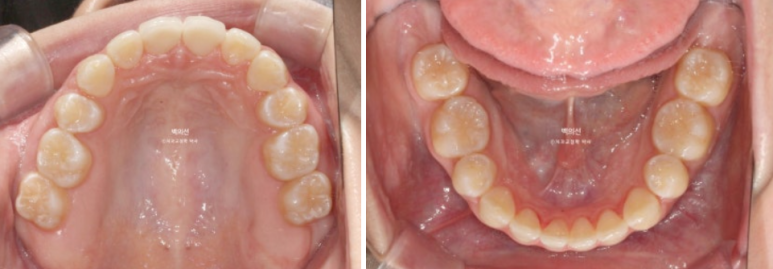

25년 3월부터 25년 6월까지 인비절라인 장치 14개를 다 낀 후 모습입니다.

25.06

중심선을 잘 맞아졌으며

남아있던 발치공간도 깔끔하게 사라졌습니다.

인비절라인라이트는 추가장치 제작의 기회가 1번 있지만 경과가 좋아 재제작 없이 치료를 마무리 하였습니다.